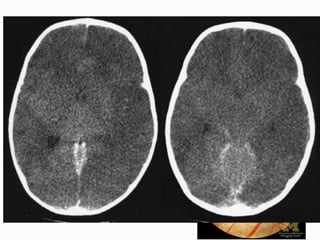

• Hemorragia petequial en

parénquima

• Imágenes Hiperdensas

Lesión Axonal Difusa •Severa (rápido edema) • Axotomía: Interrumpe Axones de Sust. Blanca- Tronco E • Etiología: desaceleración Repentina (cizallamiento) • Choques, Maltrato infantil • A veces: déficit Neurológico Irreversible cizallamiento

• Hemorragia petequialen parénquima • Imágenes Hiperdensas